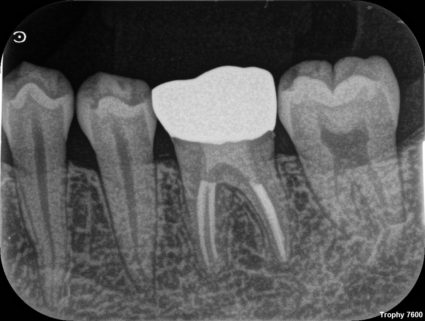

1980年代半ばに、歯冠修復の失敗によって根管充填された根管内に細菌感染が起こることが注目されるようになりました。1995年、RayとTropeによって歯内療法の質と歯冠修復の質が予後に及ぼす影響について大規模な調査が行われました。テンプル大学で治療を行った1010本の根管治療歯のX線写真を調査し、歯内療法の質と歯冠修復の質、根尖部の状態を評価しました。尚、ポストのある歯は除外されました。評価基準は以下のとおりです。

① Good Restoration・Good Endo

② GoodRestoration ・ PoorEndo

③ PoorRestoration ・ GoodEndo

④:PoorRestoration ・ Poor Endo

結果は以下のとおりです。根尖周囲炎がない割合を%で表しています。

①:GoodRestoration ・ Good Endo:91.4%、

④:PoorRestoration ・ Poor Endo:18.1%、

歯内療法と歯冠修復の質のどちらも良ければ良い結果に、どちらも悪ければ悪い結果となりました。これは明らかだと思いますが、

②:GoodRestoration ・ PoorEndo:67.6%、

③:PoorRestoration ・ GoodEndo:44.1%、

となり、この調査では「歯内療法の質よりも歯冠修復の質の方が予後に大きな影響を及ぼす」ことが分かりました。根っこの治療の質が良くなくても被せ物がピッタリ合って入れば根っこの周りに病気ができないという少々意外な結果となりました。